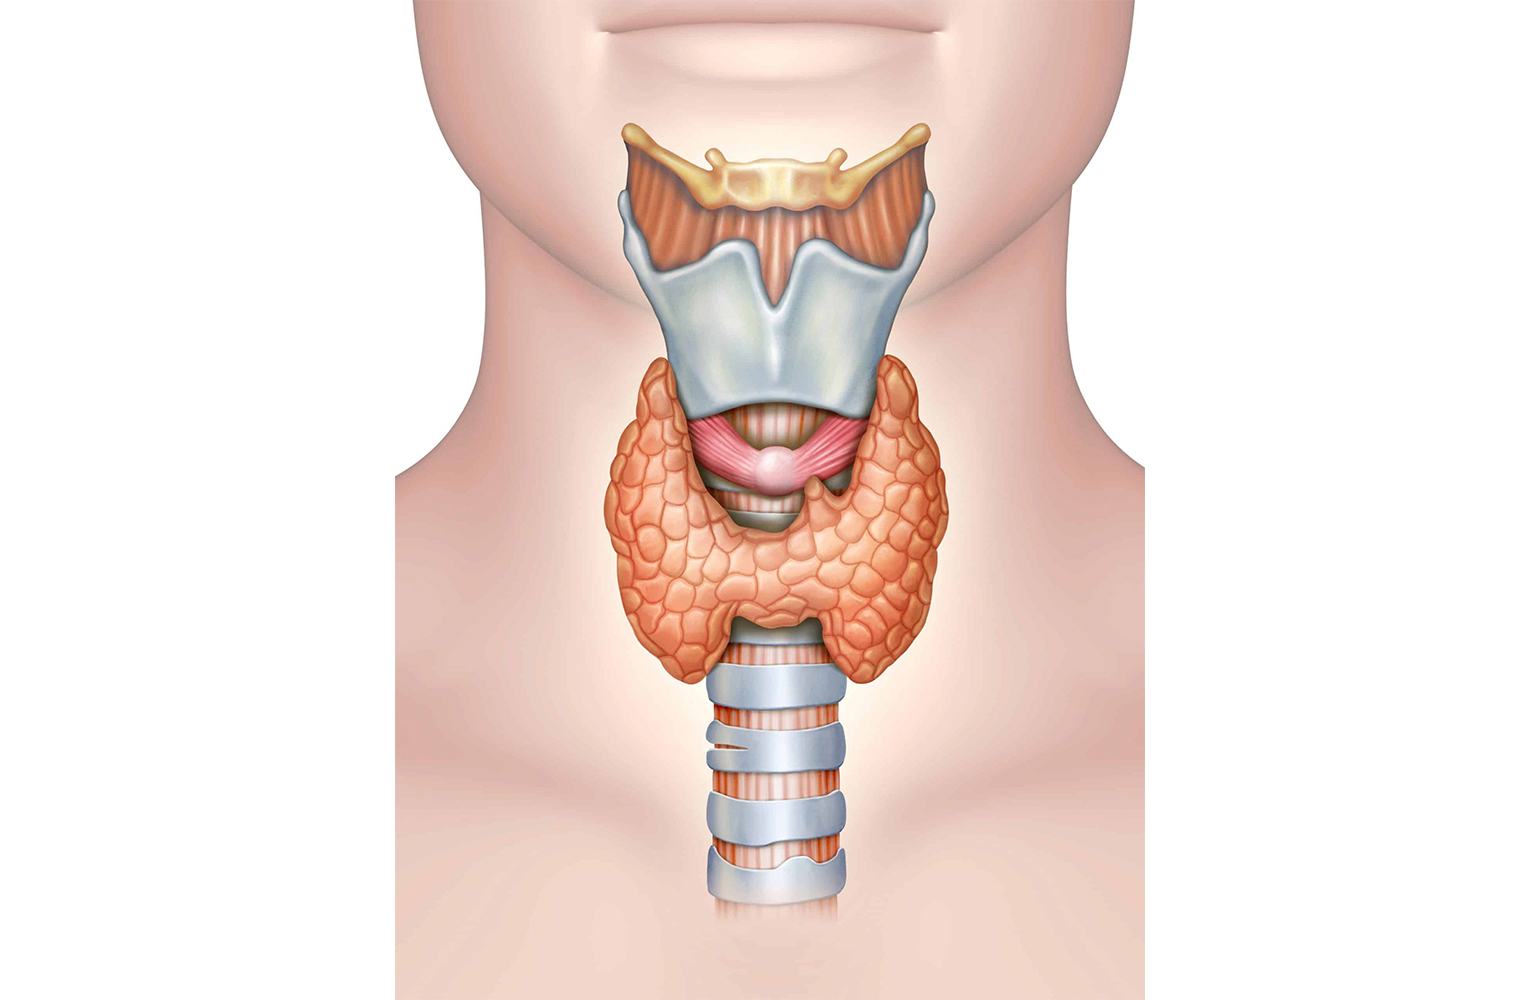

Detaylı BilgiTiroid Kanseri

Tiroid kanseri, tiroid bezinin yapısını oluşturan hücrelerin kontrolsüz bölünmeye başlamasıyla oluşan malign doku olarak tanımlanır.